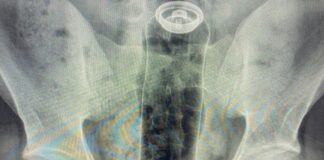

Paciente é hospitalizado após inserir desodorante no ânus durante brincadeira sexual